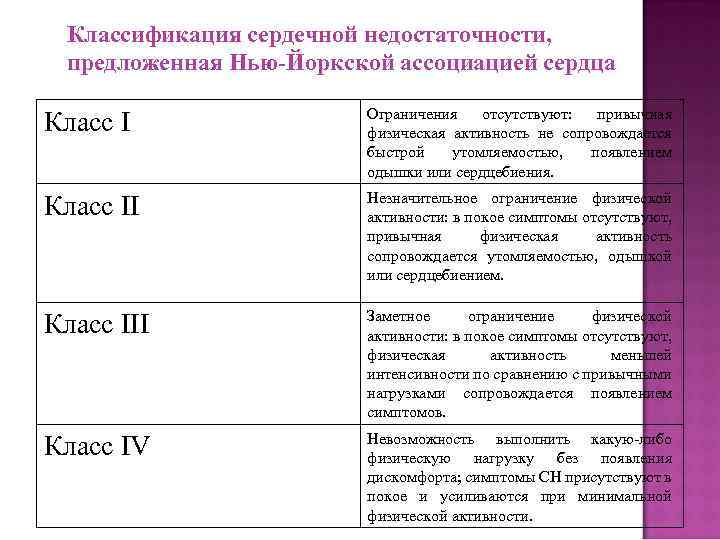

Классификация сердечной недостаточности, предложенная Нью-Йоркской ассоциацией сердца Класс I Ограничения отсутствуют: привычная физическая активность не сопровождается быстрой утомляемостью, появлением одышки или сердцебиения. Класс II Незначительное ограничение физической активности: в покое симптомы отсутствуют, привычная физическая активность сопровождается утомляемостью, одышкой или сердцебиением. Класс III Заметное ограничение физической активности: в покое симптомы отсутствуют, физическая активность меньшей интенсивности по сравнению с привычными нагрузками сопровождается появлением симптомов. Класс IV Невозможность выполнить какую-либо физическую нагрузку без появления дискомфорта; симптомы СН присутствуют в покое и усиливаются при минимальной физической активности.

Классификация сердечной недостаточности, предложенная Нью-Йоркской ассоциацией сердца Класс I Ограничения отсутствуют: привычная физическая активность не сопровождается быстрой утомляемостью, появлением одышки или сердцебиения. Класс II Незначительное ограничение физической активности: в покое симптомы отсутствуют, привычная физическая активность сопровождается утомляемостью, одышкой или сердцебиением. Класс III Заметное ограничение физической активности: в покое симптомы отсутствуют, физическая активность меньшей интенсивности по сравнению с привычными нагрузками сопровождается появлением симптомов. Класс IV Невозможность выполнить какую-либо физическую нагрузку без появления дискомфорта; симптомы СН присутствуют в покое и усиливаются при минимальной физической активности.